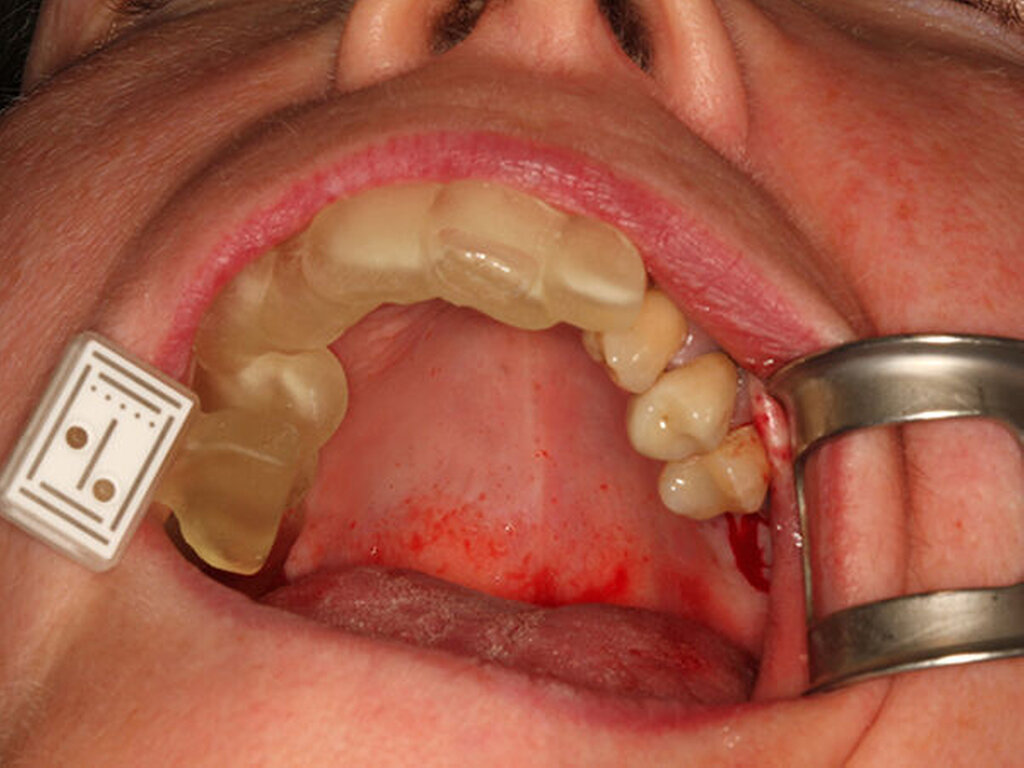

Digital erstellte Gaumenplatte für den Kiefer eines Neugeborenen

Das Tübinger Team behandelt regelmäßig mittels digitalem Workflow erstellter Behandlungsapparaturen Neugeborene und Kleinkinder, welche an angeborenen kraniofazialen Fehlbildungen leiden.

Im interdisziplinären Team von Neonatologie und Kieferorthopädie wurde das schonende Behandlungskonzept der „Tübinger Gaumenplatte“ (TPP, Tübingen palatal plate) genutzt, um invasive Therapieoptionen zu vermeiden. Bei der TPP wird eine spezielle Gaumenplatte mit velarer Extension in Mundhöhle und Pharynx eingeführt; diese wirkt der Obstruktion der oberen Atemwege entgegen, indem sie den Zungengrund nach vorn drückt.

Mittels einer Endoskopie wurden weitere Ursachen einer Atmungsstörung ausgeschlossen, wobei gleichzeitig Form und Größe des Plattensporns am additiv gefertigten Prototypen überprüft wurden. Mit einem Intraoralscanner wurden im Oberkiefer die Daten für die Gaumenplatte gewonnen. Durch deren Konstruktion wirkt sie der Verengung der Atemwege entgegen (Abbildungen 3, 4).

Mit dem digitalen Workflow konnten verschiedene Konfigurationen der Gaumenplatte entworfen und das passende Design in der Fertigung umgesetzt werden. Inkorporiert wird die Gaumenplatte vier bis sechs Monate getragen.

Konventionelle Alginat- oder Silikonabformungen hingegen zeigen sich aufgrund der Gefahr von Aspiration und Verbleib von Abformmaterialresten als komplikationsreicher und sind daher für diese Therapie in Anbetracht des Lebensalters der kleinen Patienten schlechter geeignet. Die digitale Intraoralabformung wird in Tübingen auch bei Lippen-Kiefer-Gaumenspalte und Trisomie 21 (Down-Syndrom) standardmäßig erfolgreich für die Erstellung von Apparaturen eingesetzt.